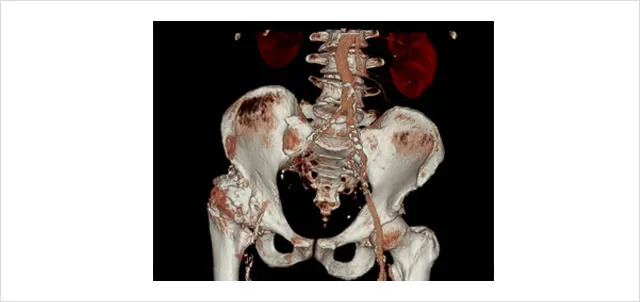

CT血管造影

造影剤を用いてCT撮影を行い、コンピューターで画像処理を行って血管の状態を見ます。写真では右足の血管が閉塞しています。